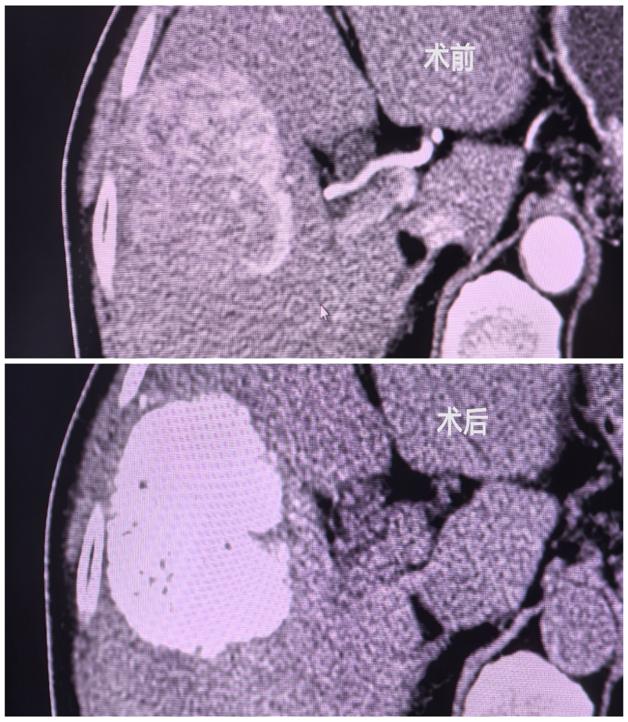

患者魏大爷在去年的体检中发现了肝脏占位性病变,但当时并未引起足够的重视。直至今年九月再次体检,发现肿块直径已惊人地增长至8厘米,遂来pilipili 消化内科就诊。结合魏大爷的乙肝小三阳病史,以及食欲减退、全身乏力的临床表现,接诊医生初步诊断为肝癌。消化内科温育鹏主任对患者病情进行了全面考量,在获得家属同意的前提下,与介入科医师刘稳棠多次深入交流,最终决定采用“肝动脉化疗栓塞术”进行治疗。在刘稳棠医生的精确操作下,手术得以顺利实施。术后,患者在医护人员的悉心护送下安全返回病房,次日开始便能下床活动,未出现明显不适,日常生活未受到显著影响。

通过DSA造影找出显影的肿瘤供血动脉

微导管超选找到肿瘤供养血管,透视下缓慢注入碘油化疗栓塞乳剂及栓塞微球栓塞肿瘤责任血管

术后显示肿瘤供血动脉减少、消失,瘤体内碘油乳剂沉积良好